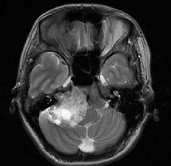

[单选题]女,45岁,右耳听力下降半年余,CT检查如图,最可能诊断为()A.继发性胆脂瘤B.脑膜瘤C.三叉神经瘤D.原发性胆脂瘤E.听神经瘤

[单选题]女,45岁,右耳听力下降半年余,CT检查如图,最可能的诊断是()A.继发性胆脂瘤B.脑膜瘤C.三叉神经瘤D.原发性胆脂瘤E.听神经瘤

[单选题]女,45岁,右耳听力下降半年余,CT检查如图,最可能的诊断是A.继发性胆脂瘤B.脑膜瘤C.三叉神经瘤D.原发性胆脂瘤E.听神经瘤

[单选题]女,45岁,右耳听力下降半年余,CT检查如图,最可能的诊断是( )。A.继发性胆脂瘤B.脑膜瘤C.三叉神经瘤D.原发性胆脂瘤E.听神经瘤